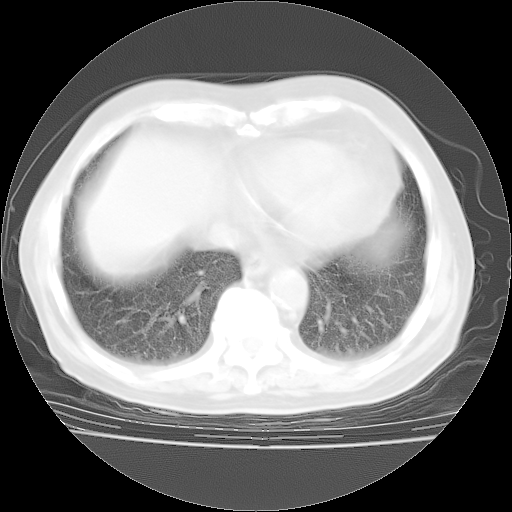

今天部分检查

轻微咳嗽,无痰,(体温正常时)R20次/分,P75次/分,双肺底、腋下可闻及少量捻发音。下肢轻度浮肿。

血常规:白细胞9.11×109/L,N0.92,L5.64,血小板39.2×109/L,HB148g/L,ESR2mm/H。

尿常规:潜血+

血生化:总蛋白69.71g/L,白蛋白38.40g/L,球蛋白31.31g/L,CRP27.9mg/L,尿素氮11.98mmol/L,肌酐106μmol/L,乳酸脱氢酶1099 U/L,肌酸激酶108U/L,CK-MB 61U/L。

腹部B超:胆囊壁增厚,肝、胆、胰、脾、肾无异常,肠系膜淋巴结、腹膜后淋巴结无增大。

ECG:右心室增大

心脏超声检查:无右心室增大。

增加治疗:异烟肼、利福平、乙胺丁醇,静滴左氧氟沙星、参麦注射液。甲强龙从80mg暂减为40mg。

强的松3月1日改为10mg qd,4月1日改为10mg qod。3月份以前的减量过程和环磷酰胺疗程需等明天查看记录(我岳父自己做的记录在他家里)。